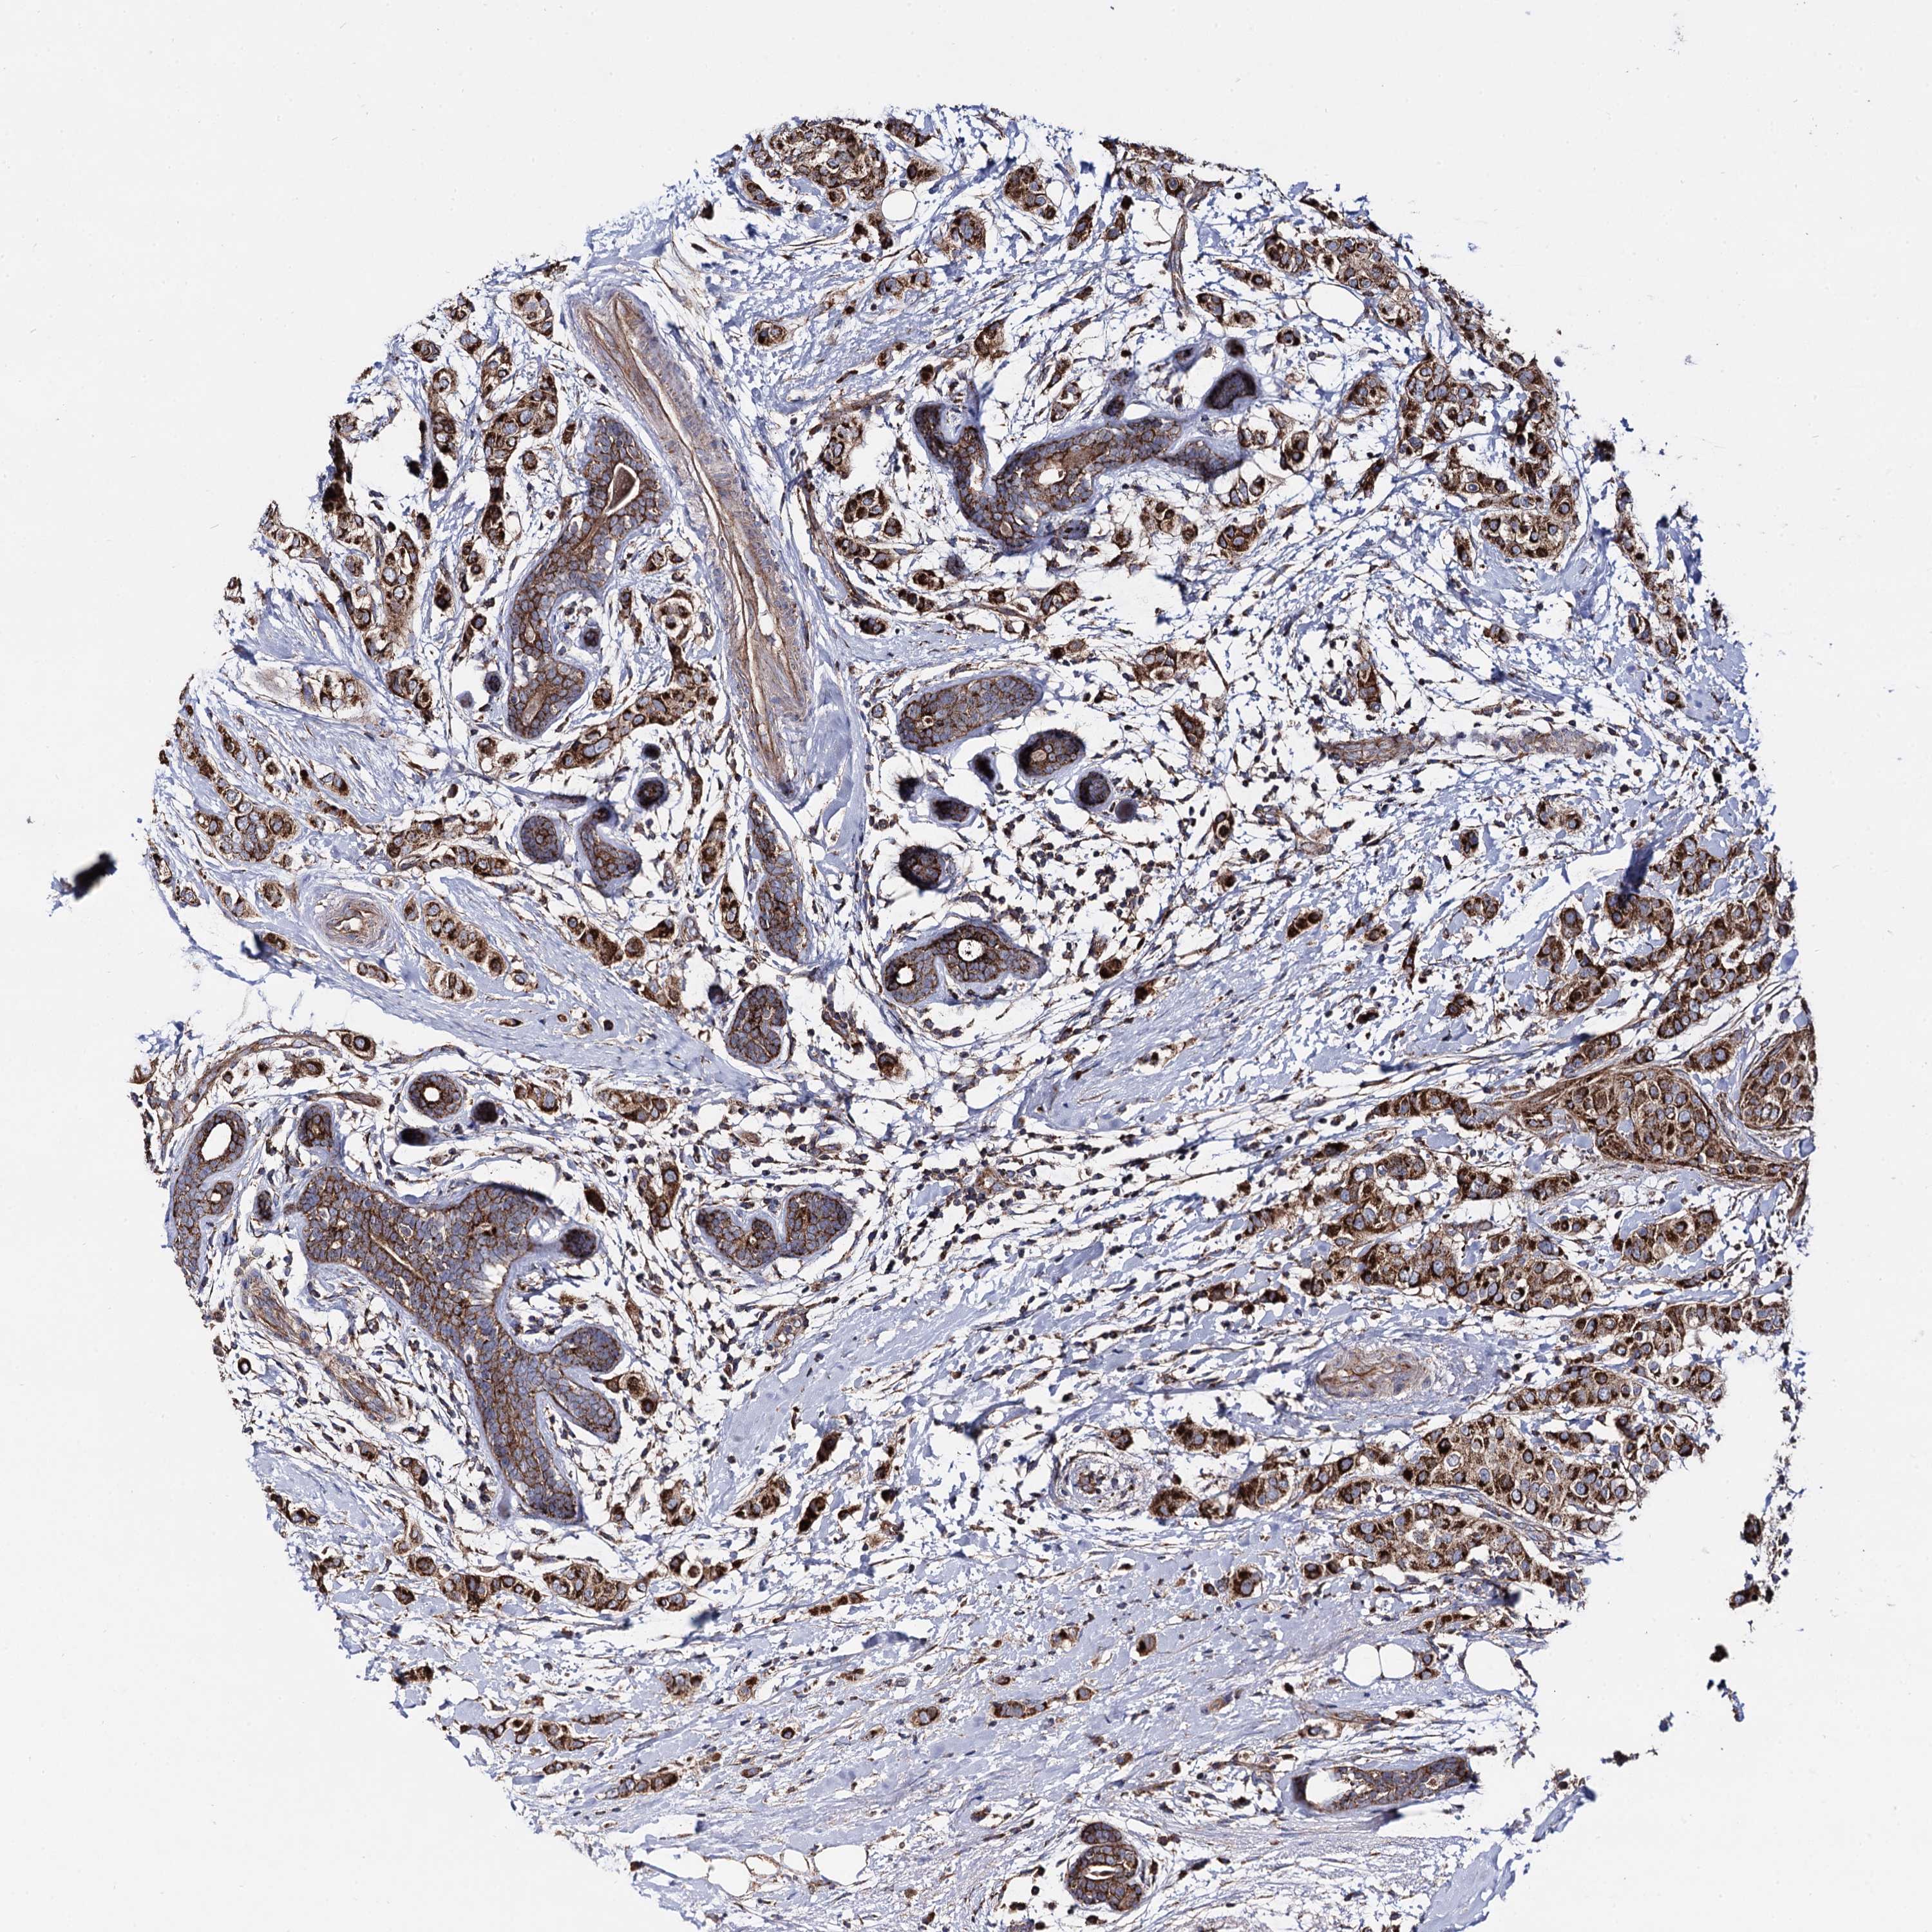

CANCER BREAST CANCER Show tissue menu

BRCA TCGA BRCA VALIDATION PROTEIN EXPRESSION